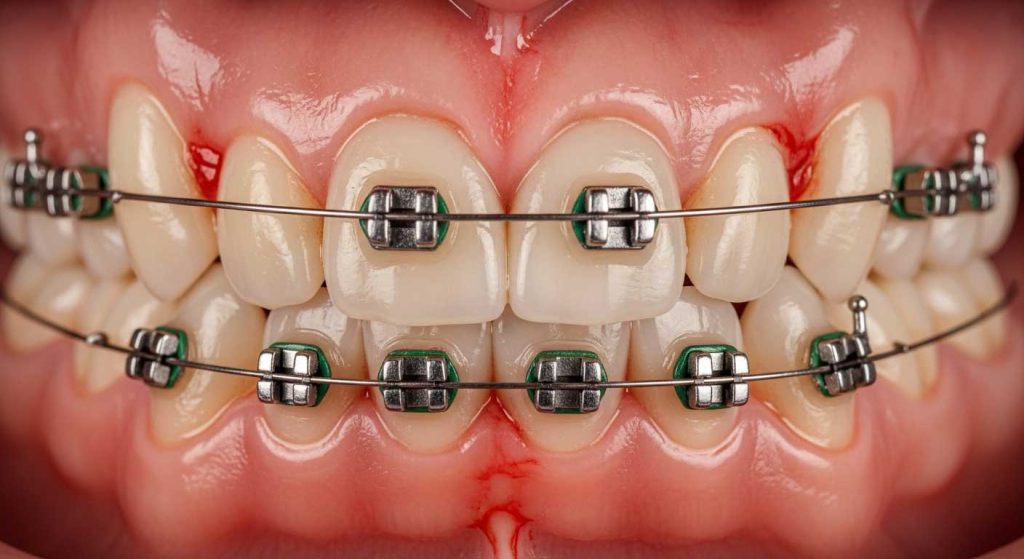

التهاب لثه در ارتودنسی که در علم دندانپزشکی به آن ژنژیویت ناشی از پلاک گفته می شود، یک واکنش التهابی بافت لثه به تجمع پلاک های باکتریایی است. این وضعیت اولین و خفیف ترین مرحله از بیماری های لثه است و خوشبختانه با رعایت بهداشت و درمان های مناسب، کاملاً قابل برگشت است. پلاک یک لایه نرم و چسبنده از باکتری هاست که اگر به طور منظم حذف نشود، می تواند باعث تحریک لثه ها و آزاد شدن سمومی شود که منجر به پاسخ التهابی بدن می گردد.

- قرمزی و تورم: لثه ها از رنگ صورتی مرجانی سالم به قرمز روشن یا حتی بنفش تغییر رنگ داده و پف کرده و متورم به نظر می رسند. این تورم می تواند باعث شود لبه های لثه از حالت تیز و مثلثی بین دندان ها، به حالتی گرد و پف کرده تغییر شکل دهند.

- خونریزی: شایع ترین و اولین علامت، خونریزی لثه ها هنگام مسواک زدن یا نخ کشیدن است. حتی ممکن است هنگام خوردن غذا های کمی سفت نیز لثه ها خونریزی کنند. لثه سالم نباید به راحتی خونریزی کند.

بریس ارتودنسی، شامل براکت ها، سیم ها، لیگاچور ها و کش ارتودنسی، سطوح ناهموار و فضا های کوچک متعددی را روی دندان ها ایجاد می کند. این نواحی به پناهگاه هایی ایده آل برای ذرات غذا و باکتری ها تبدیل می شوند. تمیز کردن کامل این نقاط با مسواک و نخ دندان معمولی بسیار دشوار است و این امر منجر به تجمع سریع پلاک ارتودنسی در اطراف براکت ها و زیر سیم می شود.